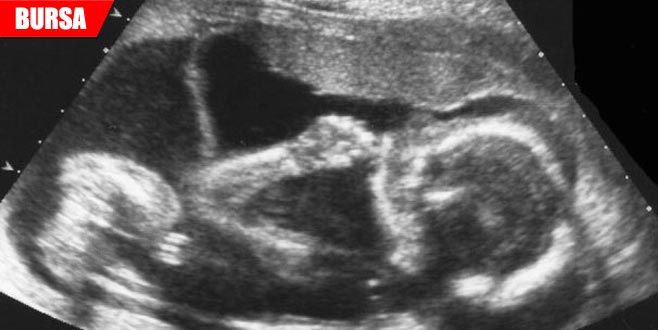

Bursa'da yaşayan Gözütok çifti, hamilelik dönemindeki kontrollerde önce bir, daha sonra ikiz ve son kontrolde üçüz olduğunu öğrendikleri bebeklerinin dünyaya gelmesinin heyecanını ve mutluluğunu yaşıyor.

İki hafta sonraki kontrolde bebeklerinin ikiz, daha sonra da üçüz olduğu söylenen çiftin üçüzleri, hamileliğin 30. haftasında dünyaya geldi.